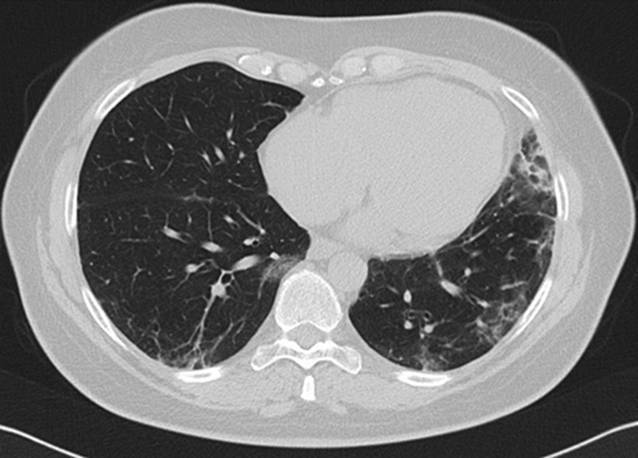

In der Computertomographie (CT) des Thorax zeigte sich nach 8 Monaten Therapie mit MMF eine Größenregredienz der subpleural, peribronchial und basal betonten Konsolidierungen (Abb. 8). Lungenfunktionell zeigte sich im Verlauf von 6 Monaten eine Besserung der restriktiven Ventilationsstörung sowie der Diffusionsstörung (Tab. 1). Somit konnte ein positiver Verlauf unter MMF bei therapierefraktärer MDA5-assoziierter Dermatomyositis mit rasch progredienter Lungenbeteiligung gezeigt werden (Abb. 9).